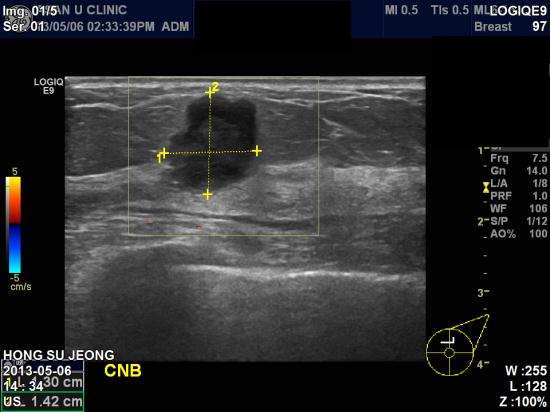

왼쪽  유방에 만져지는 혹과, 건강검진 이상소견으로 내원하신 57세 여성분이십니다.

좌측 12시 방향 유방  피부쪽에 가까운 딱딱한 혹 있어,

본원 유방초음파 시행 후 조직검사 시행하여 좌측 유방암으로 진단 되었습니다.